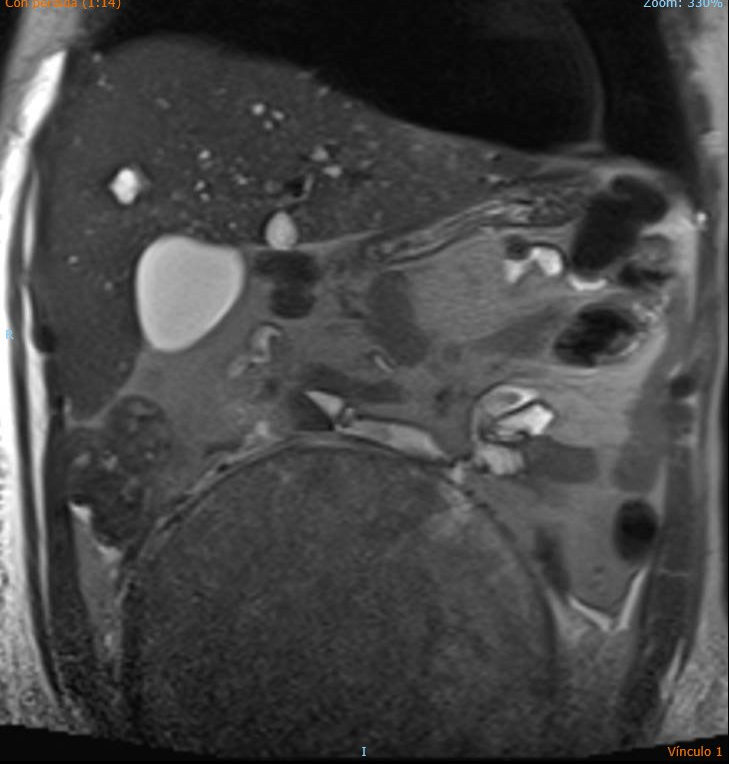

Ecografía de abdomen de Urgencias: se observa gran LOE pélvico abdominal ecogenicidad heterogénea, con hígado aumentado de tamaño y con imágenes hipoecoicas. Uterohidronefrosis derecha.

Durante el ingreso hospitalario se realizó biopsia de adenopatía que concluyó metastásis de neoplasia de estirpe germinal (posible Seminoma).

Igualmente se concluyó el estudio con ecografía de testículo y RNM.

En Atención Primaria, los meses previos fue tratado como una lumbalgia de cáracter crónico. La disnea por la que se derivó fue fruto de un TEP. El diagnóstico definitivo: Seminoma con hígado metastásico con adenopatías derechas y compresión de ilíaca derecha.